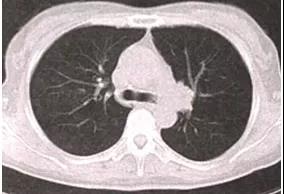

患者有结核病史。病灶多位于上叶尖后段及下叶背段,多呈球形,边界清晰,空洞、钙化常见,周围可见卫星灶。增强扫描无强化或轻度强化,持续随访多无明显改变。